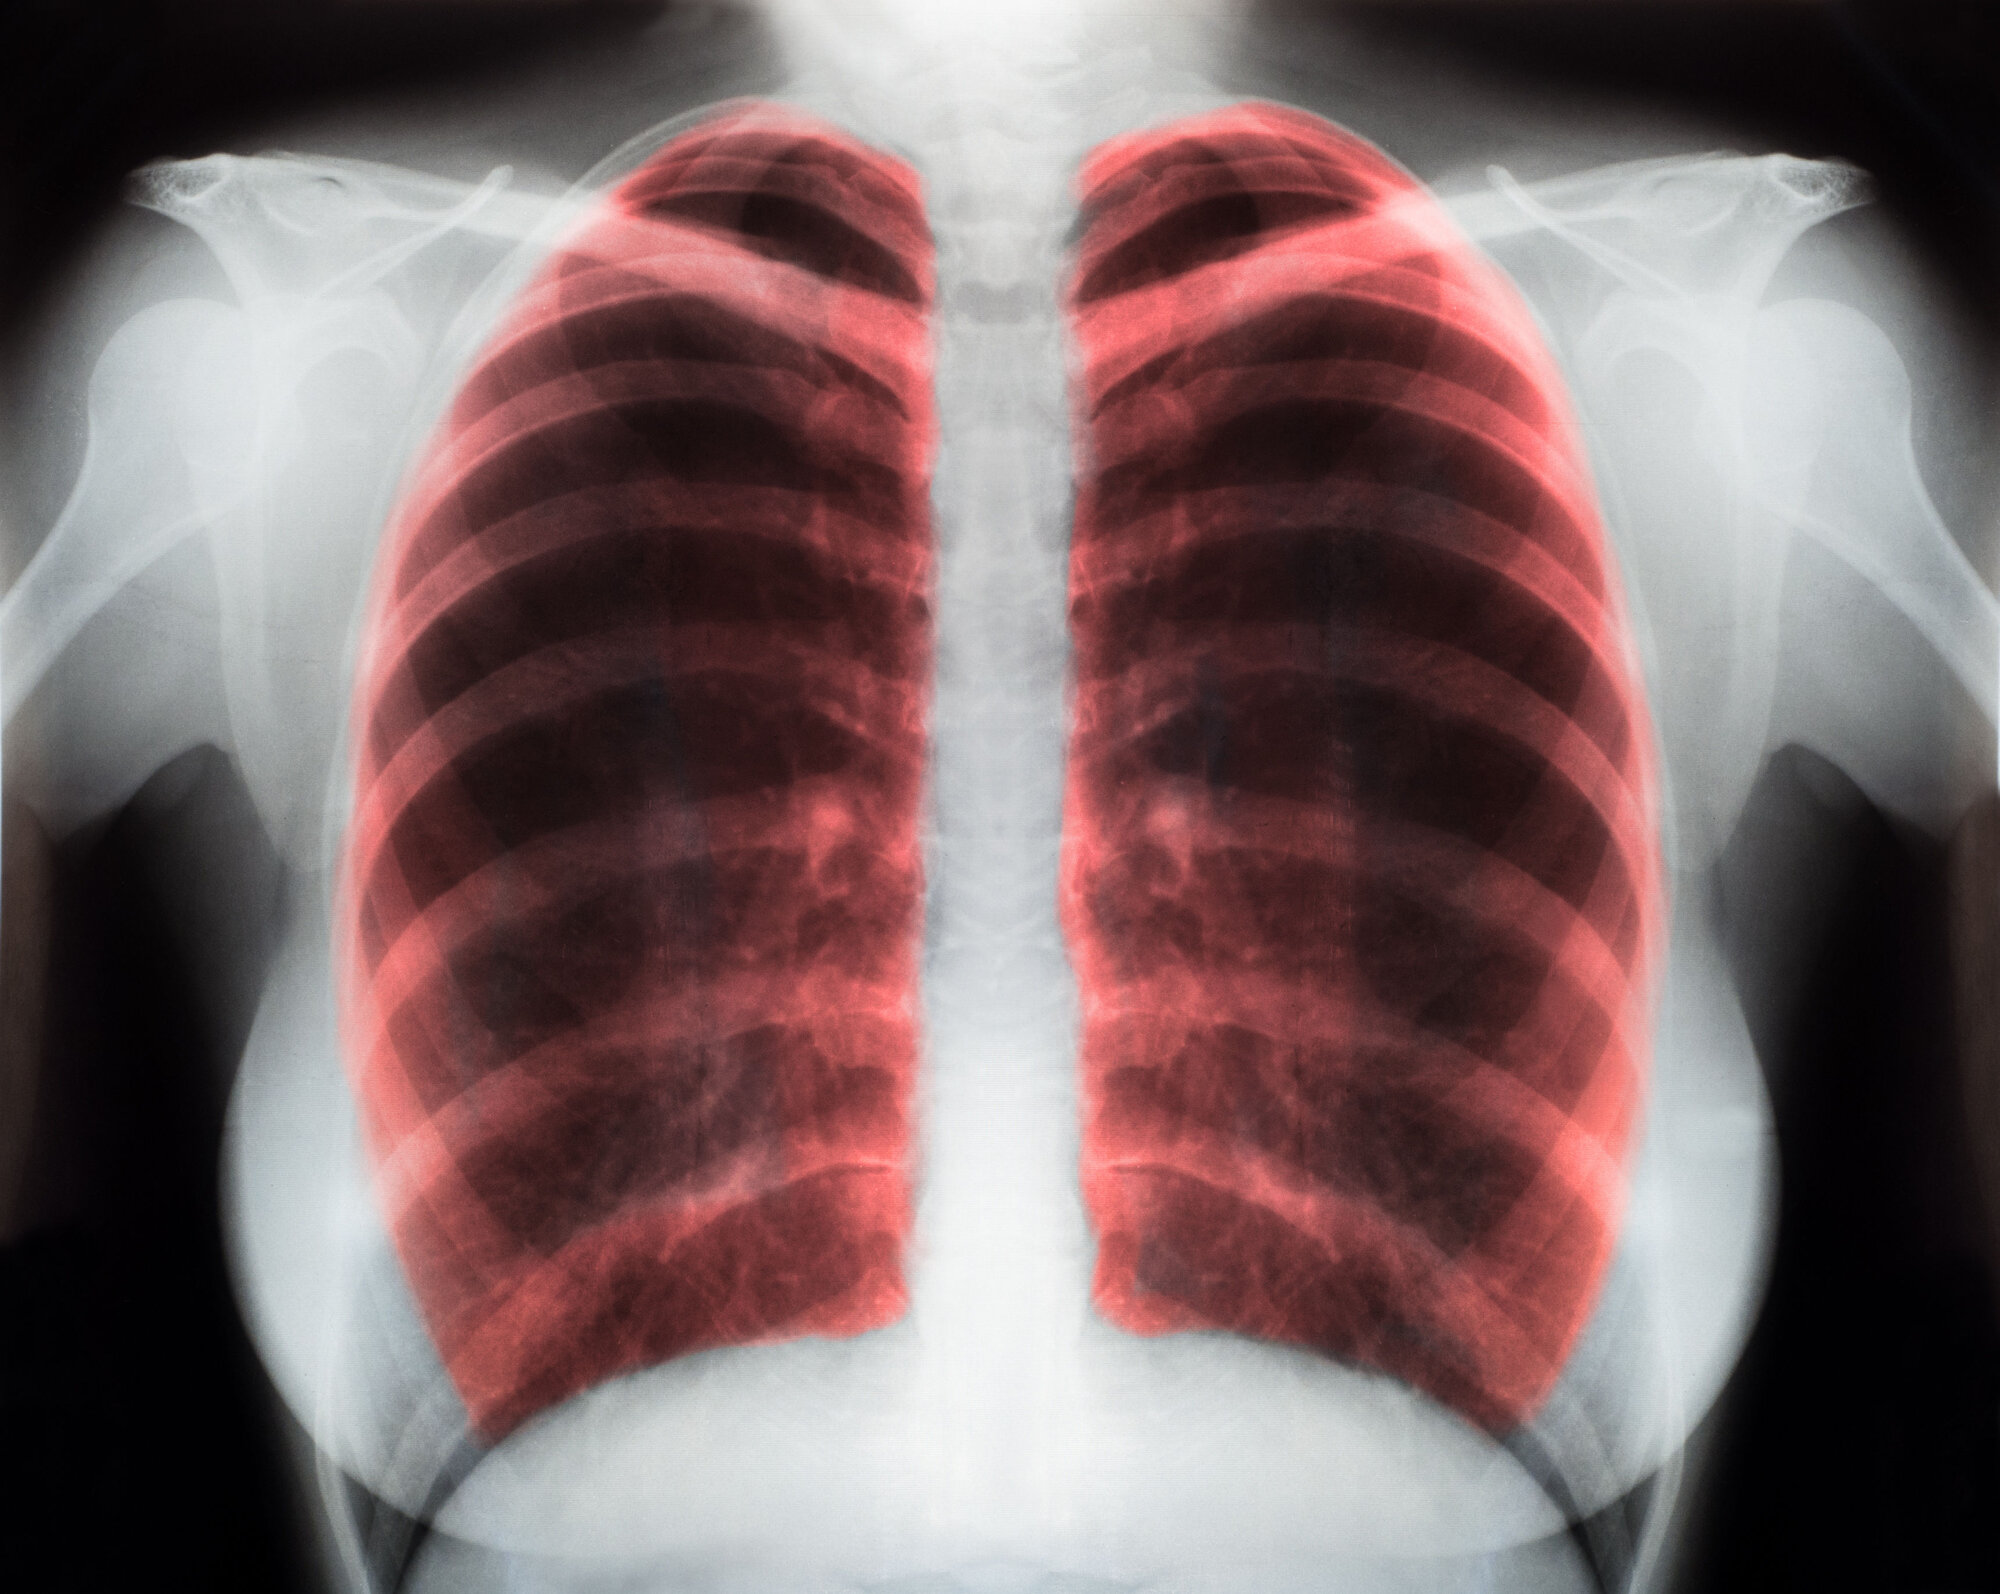

Kronisk obstruktiv lungesykdom (kols) som har fått utvikle seg til en alvorlig grad av sykdommen, vil påvirke pasientenes livskvalitet negativt med høy symptombyrde. Pasientene strever særlig med å puste, noe som begrenser deres daglige aktiviteter. Tidligere studier har vist lovende resultater ved å anvende telemedisinsk oppfølging av kolspasienter.